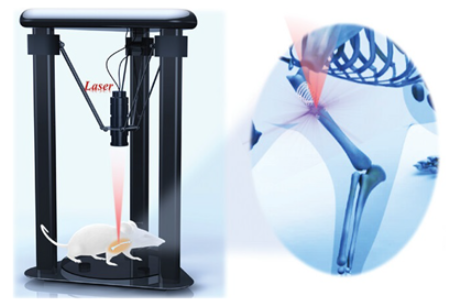

3.3. Patient-Specific Occluder

| upconversion 3D bioprinting [106] | Patient-specific 3D-printed implants; enhanced tissue integration; in vivo non-invasive fabrication. | Long-term concerns; precision challenges for bioprinting in cardiac environment; complex regulatory pathway. |

| patient-specific occluder | Customized geometry for each patient’s LAA; thin-walled, inflatable balloons made from soft, biocompatible materials; incorporates biomimetic surface patterns for enhanced adhesion; superior anchoring force and reduced leak rates in vitro. | Complex manufacturing process; challenges in ensuring consistent quality across custom devices; long-term durability of soft materials needs evaluation; potentially higher cost, due to customization. |